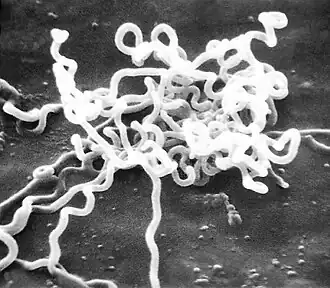

Treponema pallidum, poddruh pallidum, je spirálovitá, gramnegativní, vysoce pohyblivá bakterie.[9][14] Poddruhy příbuzné Treponema pallidum způsobují další tři lidská onemocnění, mezi něž patří frambézie (poddruh pertenue), pinta (poddruh carateum) a endemická syfilis (poddruh endemicum).[5] Oproti poddruhu pallidum však nejsou příčinou neurologických onemocnění.[13] Lidé jsou jediným známým přirozeným rezervoárem poddruhu pallidum.[6] Bez hostitele není tento poddruh schopen přežít déle než několik dnů, a to vzhledem ke svému malému genomu (1,14 MDa), který nedokáže zakódovat metabolické dráhy k většině makronutrientů. Má pomalou dobu zdvojení, která je delší než 30 hodin.[9]